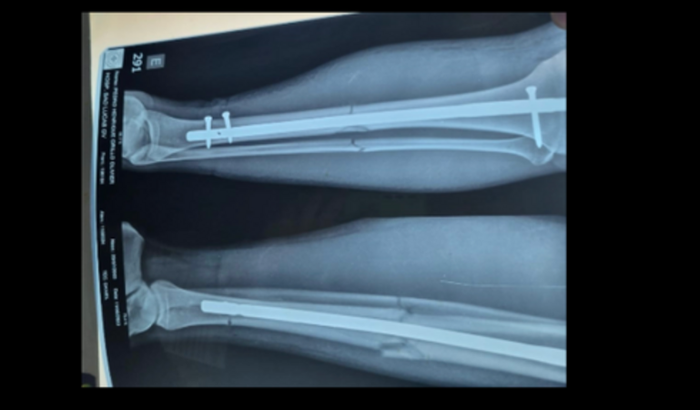

Infelizmente, nosso atleta quebrou a perna durante uma competição recente. Foi fraturado a tíbia e a fíbula dele. Essa lesão exigiu uma cirurgia complexa e um longo período de recuperação, envolvendo fisioterapia intensiva e acompanhamento médico constante. Acreditamos que, com os cuidados e apoio adequados, ele poderá voltar a trilhar o caminho do sucesso esportivo, mas sabemos que essa jornada será desafiadora, tanto emocionalmente quanto financeiramente.